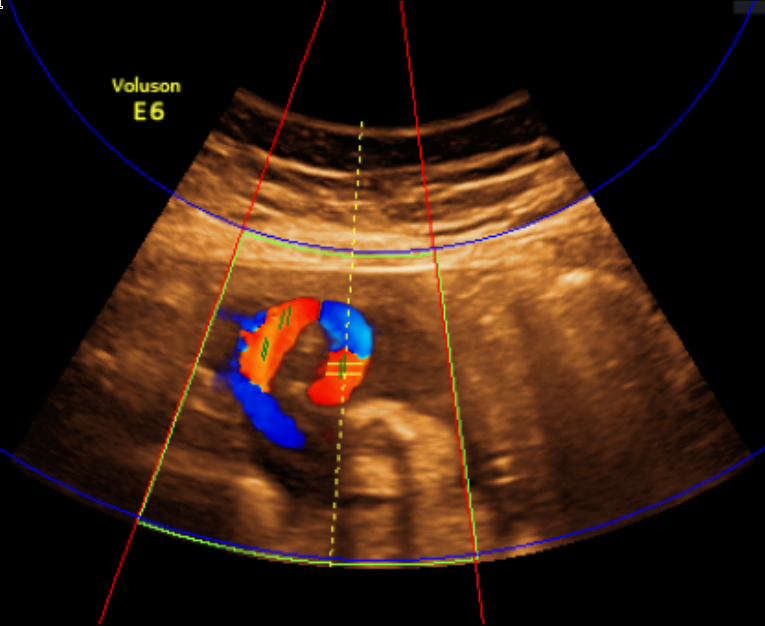

Refer to caption

(a) Expert annotated boxes and tangential lines

(b) Model predicted boxes and tangential lines

(c) Vectors pointing in direction of ultrasound source

Figure 4: Different stages in processing Color Doppler image.

Next, from the identified location of the ultrasound source, it is straightforward to compute a vector map pointing at the direction of the ultrasound source from each pixel (see Fig. 4(c)). By expressing the vessel angle predicted by the network as another vector, the angle of insonation can be easily calculated using the law of cosine.